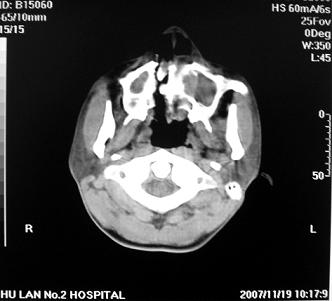

标题: CT10521:男。32岁,副鼻窦ct,请会诊。

男。32岁,鼻塞,流涕一年余。

软组织密度影填满上颌蚪 筛窦及鼻腔,并导致筛骨 上颌窦内侧壁明显骨质破坏。多考虑:内翻性乳头状瘤!

双侧鼻腔内低密度软组织影,骨壁无明显破坏,鼻腔无扩大,双侧上颌窦、筛窦软组织影,窦壁增厚,结合临床考虑鼻息肉合并慢性上颌窦炎。